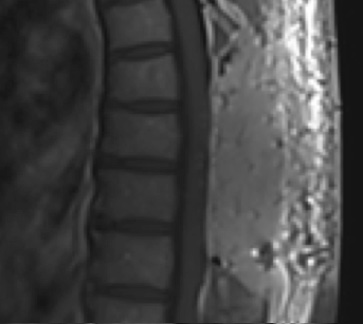

Preoperative MRI T1w demonstrating a large enhancing tumor with severe cord compression